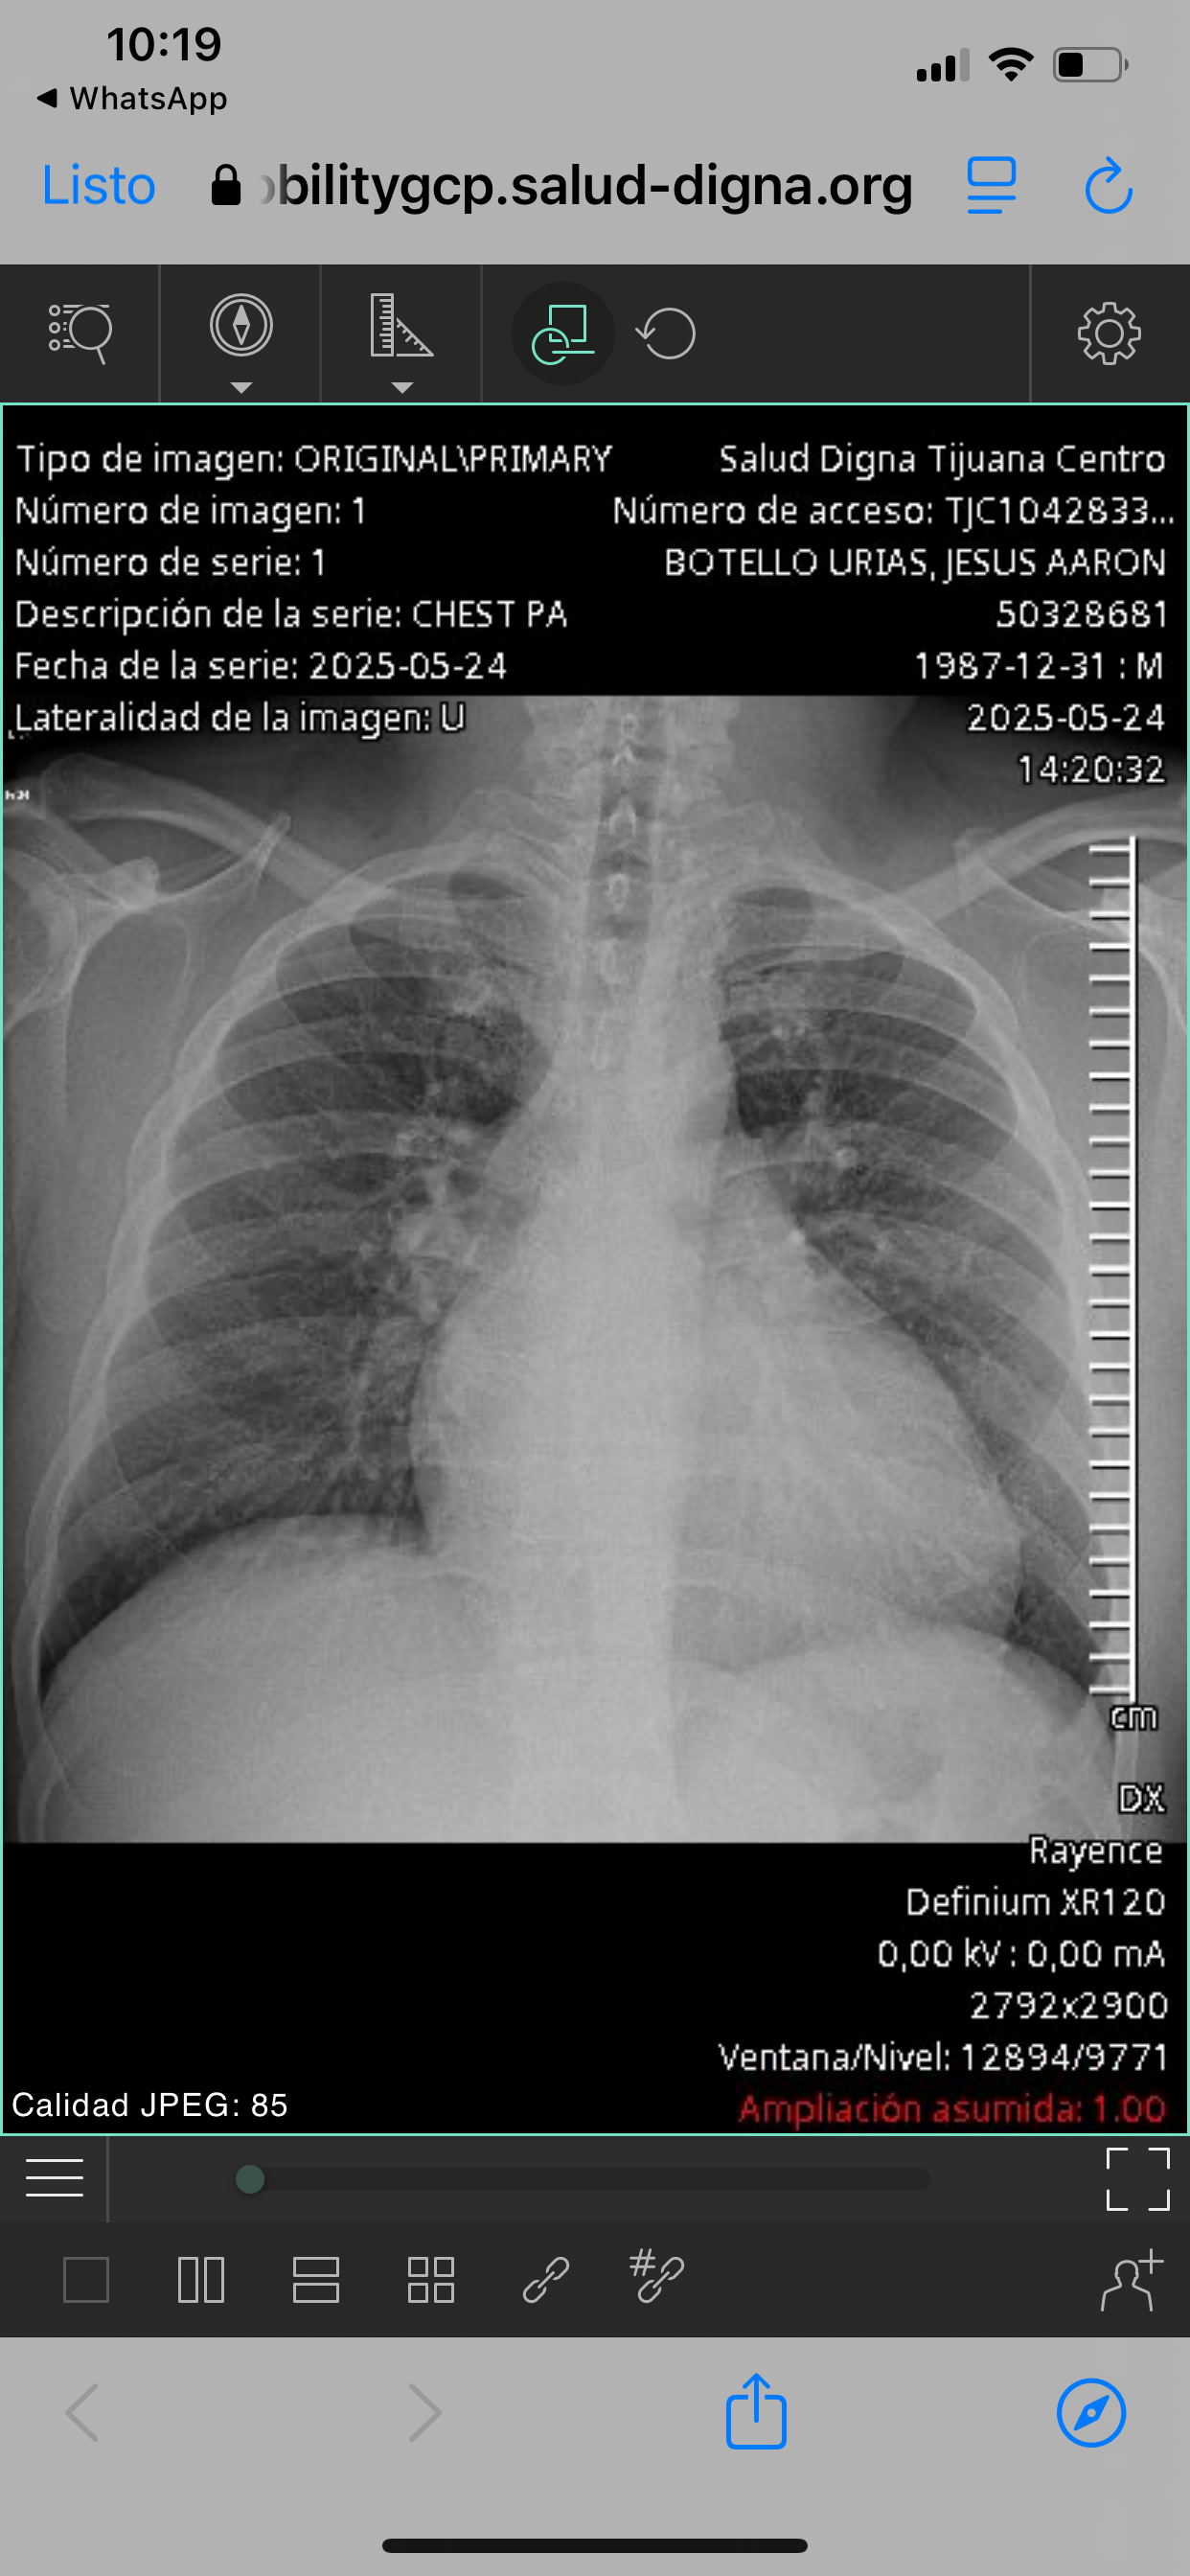

Hola me llamo Jesus aaron botello Urías tengo 37 años hace un mes dime detectaron cardiomegalia etapa 4, lo que no me permite trabajar a lo que me dedicaba (cocina).